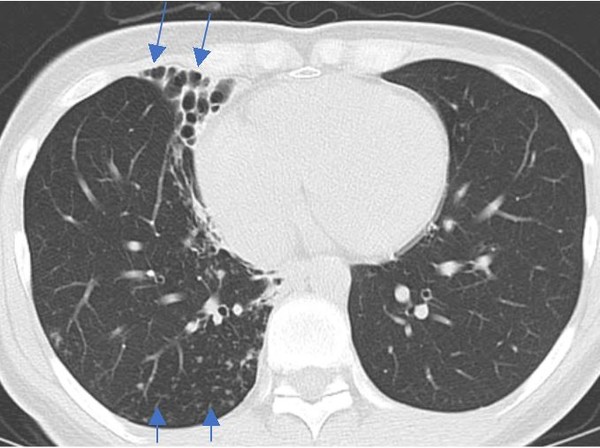

진단은 임상적인 호흡기 증상과 함께 흉부 영상 소견 및 미생물학적 균 확인 등의 결과를 종합해 판단한다. 만성 기침, 가래 혹은 객혈 등 임상 증상이 초기에는 없거나 경미할 수도 있어 건강 검진으로 시행한 흉부 영상 소견에서 진단이 의심되는 경우도 종종 있다. 흉부 영상 소견은 기관지확장증에 모세기관지염을 동반한 결절성 기관지확장증 형태나 공동을 동반한 형태로 나타날 수 있다. 특히 공동성 병변은 결핵이나 폐암에서도 보일 수 있어 감별 검사가 필요하다.